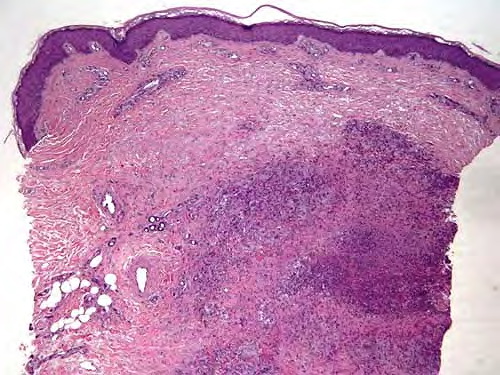

pathologic examination of tissue can reveal tuberculoid, palisading, and sarcoidlike granulomas; a diffuse infiltrate of histiocytic foamy cells; acute and chronic panniculitis; nonspecific chronic inflammation; cutaneous abscesses; suppurative granulomas; and necrotizing folliculitis. Suppurative granulomas are the most characteristic feature in skin biopsy specimens from cutaneous atypical mycobacteria infections. The evolution of the disease and the immunologic status of the host may explain this spectrum of morphologic changes.

Some authorities note severe inflammatory lesions involved with the dermis and the hypodermis; these can have 3 main histopathologic patterns: granulomatous nodular or diffuse inflammation with mixed granulomas, prevailing abscesses with mild granulomatous reaction, and deep dermal and subcutaneous granulomatous inflammation with no neutrophil component.